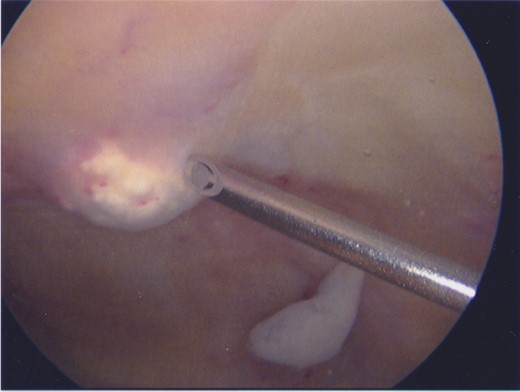

The supra-patellar pouch of the knee during arthroscopy. A focus of calcification is seen protruding into the joint, left of the tip of the needle. Note the erythematous synovitis overlying the calcification. Loose material below the needle shaft is believed to be fibrotic synovium.

The surgical procedure began with an arthroscopy. Synovitis was identified in the supra-patella pouch where foci of calcified material protruded from the quadriceps tendon. An arthroscopic shaver was used to excise calcified deposits, prior to open operation.

Arthroscopy confirmed synovitis in the supra-patella pouch in those regions where calcified material was present. This patient’s pain was likely caused by the synovitis overlying the calcific foci, rather than the calcification itself, given the rich sensory innervation of synovium [10].